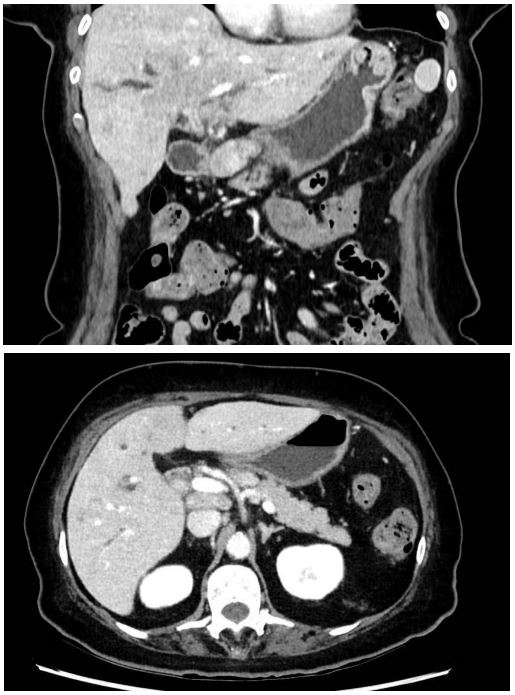

The needle biopsy returned positive for a lymphatic ganglion exhibiting lymphoproliferation B CD 20-, CD 30+, CD15 -/+ EBV+, suggestive in the first instance of classical Hodgkin’s lymphoma. The positron emission tomography revealed multiple hypermetabolic lymph nodes, liver, bone and lung lesions, as well as splenomegaly with diffuse splenic hypermetabolism and multiple focal splenic hypermetabolic lesions, consistent with lymphomatous involvement (Figure 3). The diagnosis of classical Hodgkin’s lymphoma was confirmed with incisional biopsy on a hypermetabolic right axillary lymph node.

Figure 3: PET CT scan.